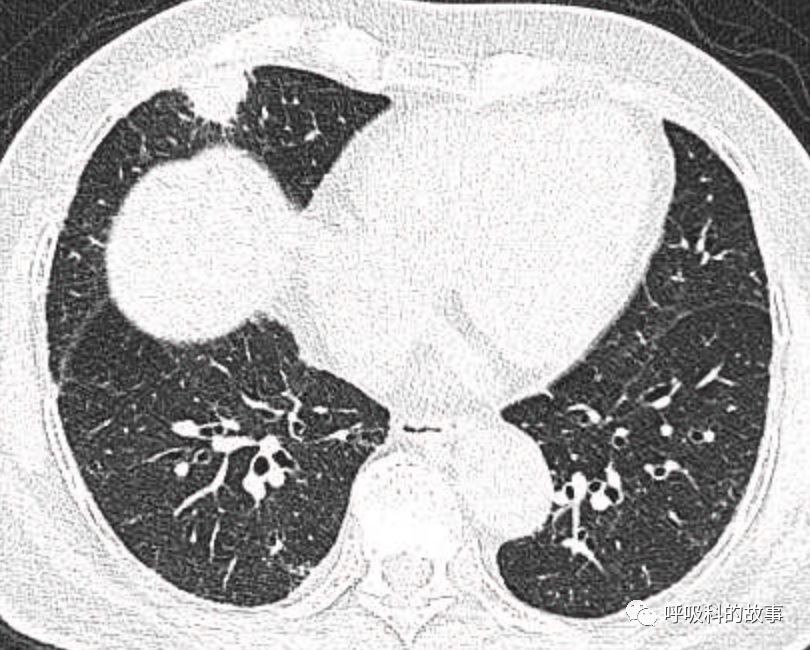

可是就在今年初,患者曾住在某院某科室,因为其他内科疾病住院。当时肺部CT也发现了在右中叶内侧段的高密度实变影,由于影像很类似肺炎,因此当成肺炎治疗。

图12-14:该患者各个角度的影像图像

(上下滑动查看全部图片)